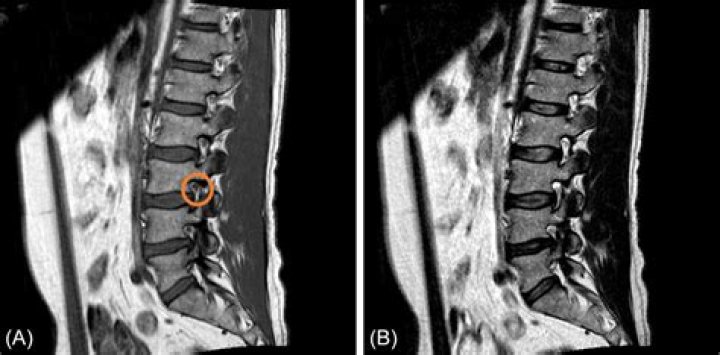

Conclusions. Inflammatory MRI lesions in early AS are seen more often in posterior structures of the spine. This may be relevant for the diagnosis of early AS and the early detection of inflammatory spinal involvement.